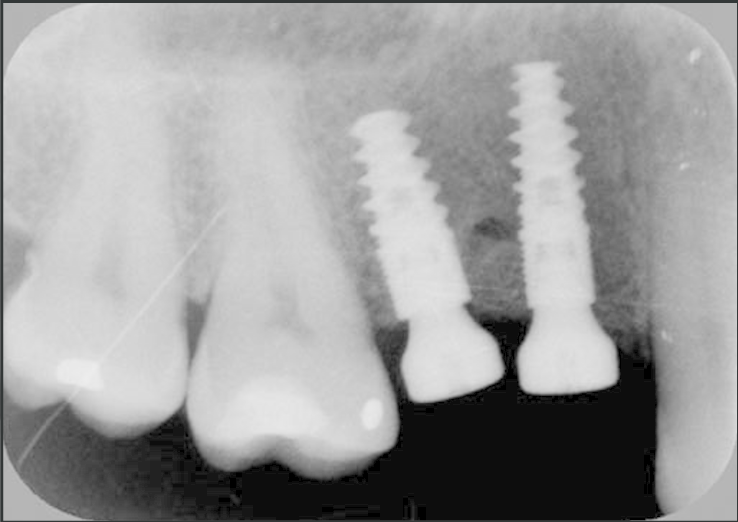

4.Colocación del implante: Realizada por un especialista en un cirugía.

5.Osteointegración: El implante debe fusionarse con el hueso y estabilizarse aprox. 3-6 meses